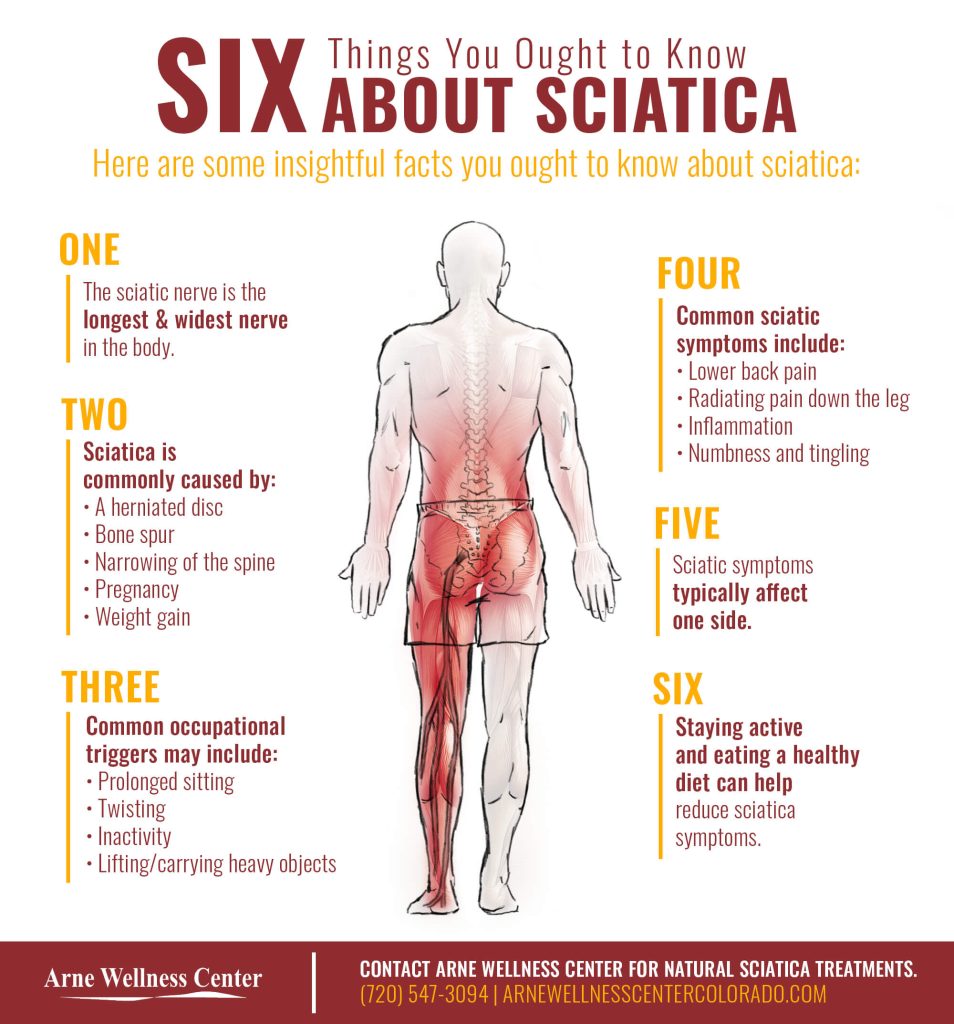

Download Sciatic nerve pain pictures